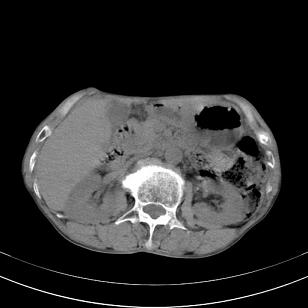

标题: 男,65岁,反复右上腹痛, [打印本页]

标题: 男,65岁,反复右上腹痛,

胃镜提示十二指肠占位